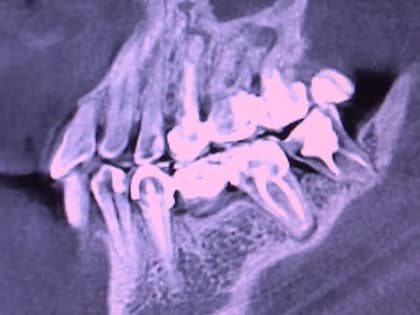

Зубы и десны влияют на состояние здоровья

Правильный уход за полостью рта поможет избежать серьезных заболеваний. Накануне Дня стоматолога, который отмечается 9-го февраля, мы встретились с врачами 29-ой больницы.